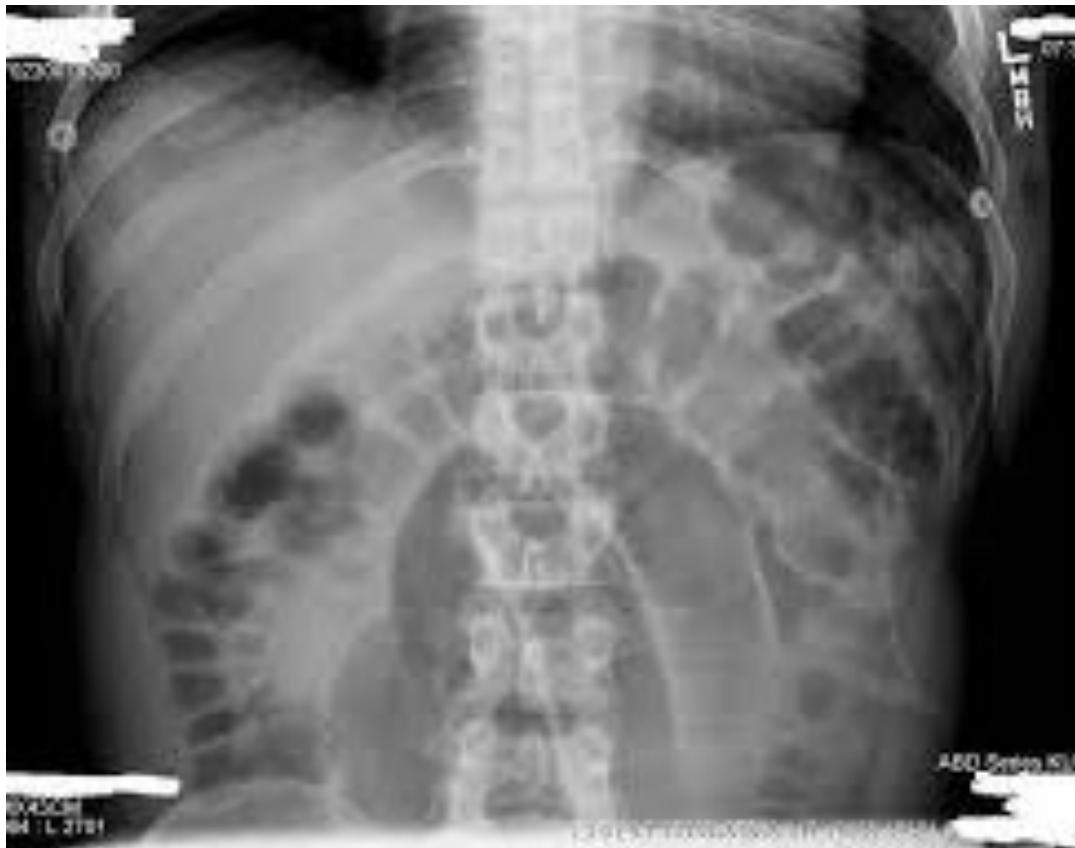

Volvulus

- Diagnosis: Volvulus (Sigmoid or Cecal).

- Cause: Malrotation or twisting of the bowel.

- Risk Factors:

- Chronic constipation.

- Abdominal adhesions.

- Hirschsprungโs disease.

- Common in elderly or bedridden patients.

- Management: Surgical emergency.